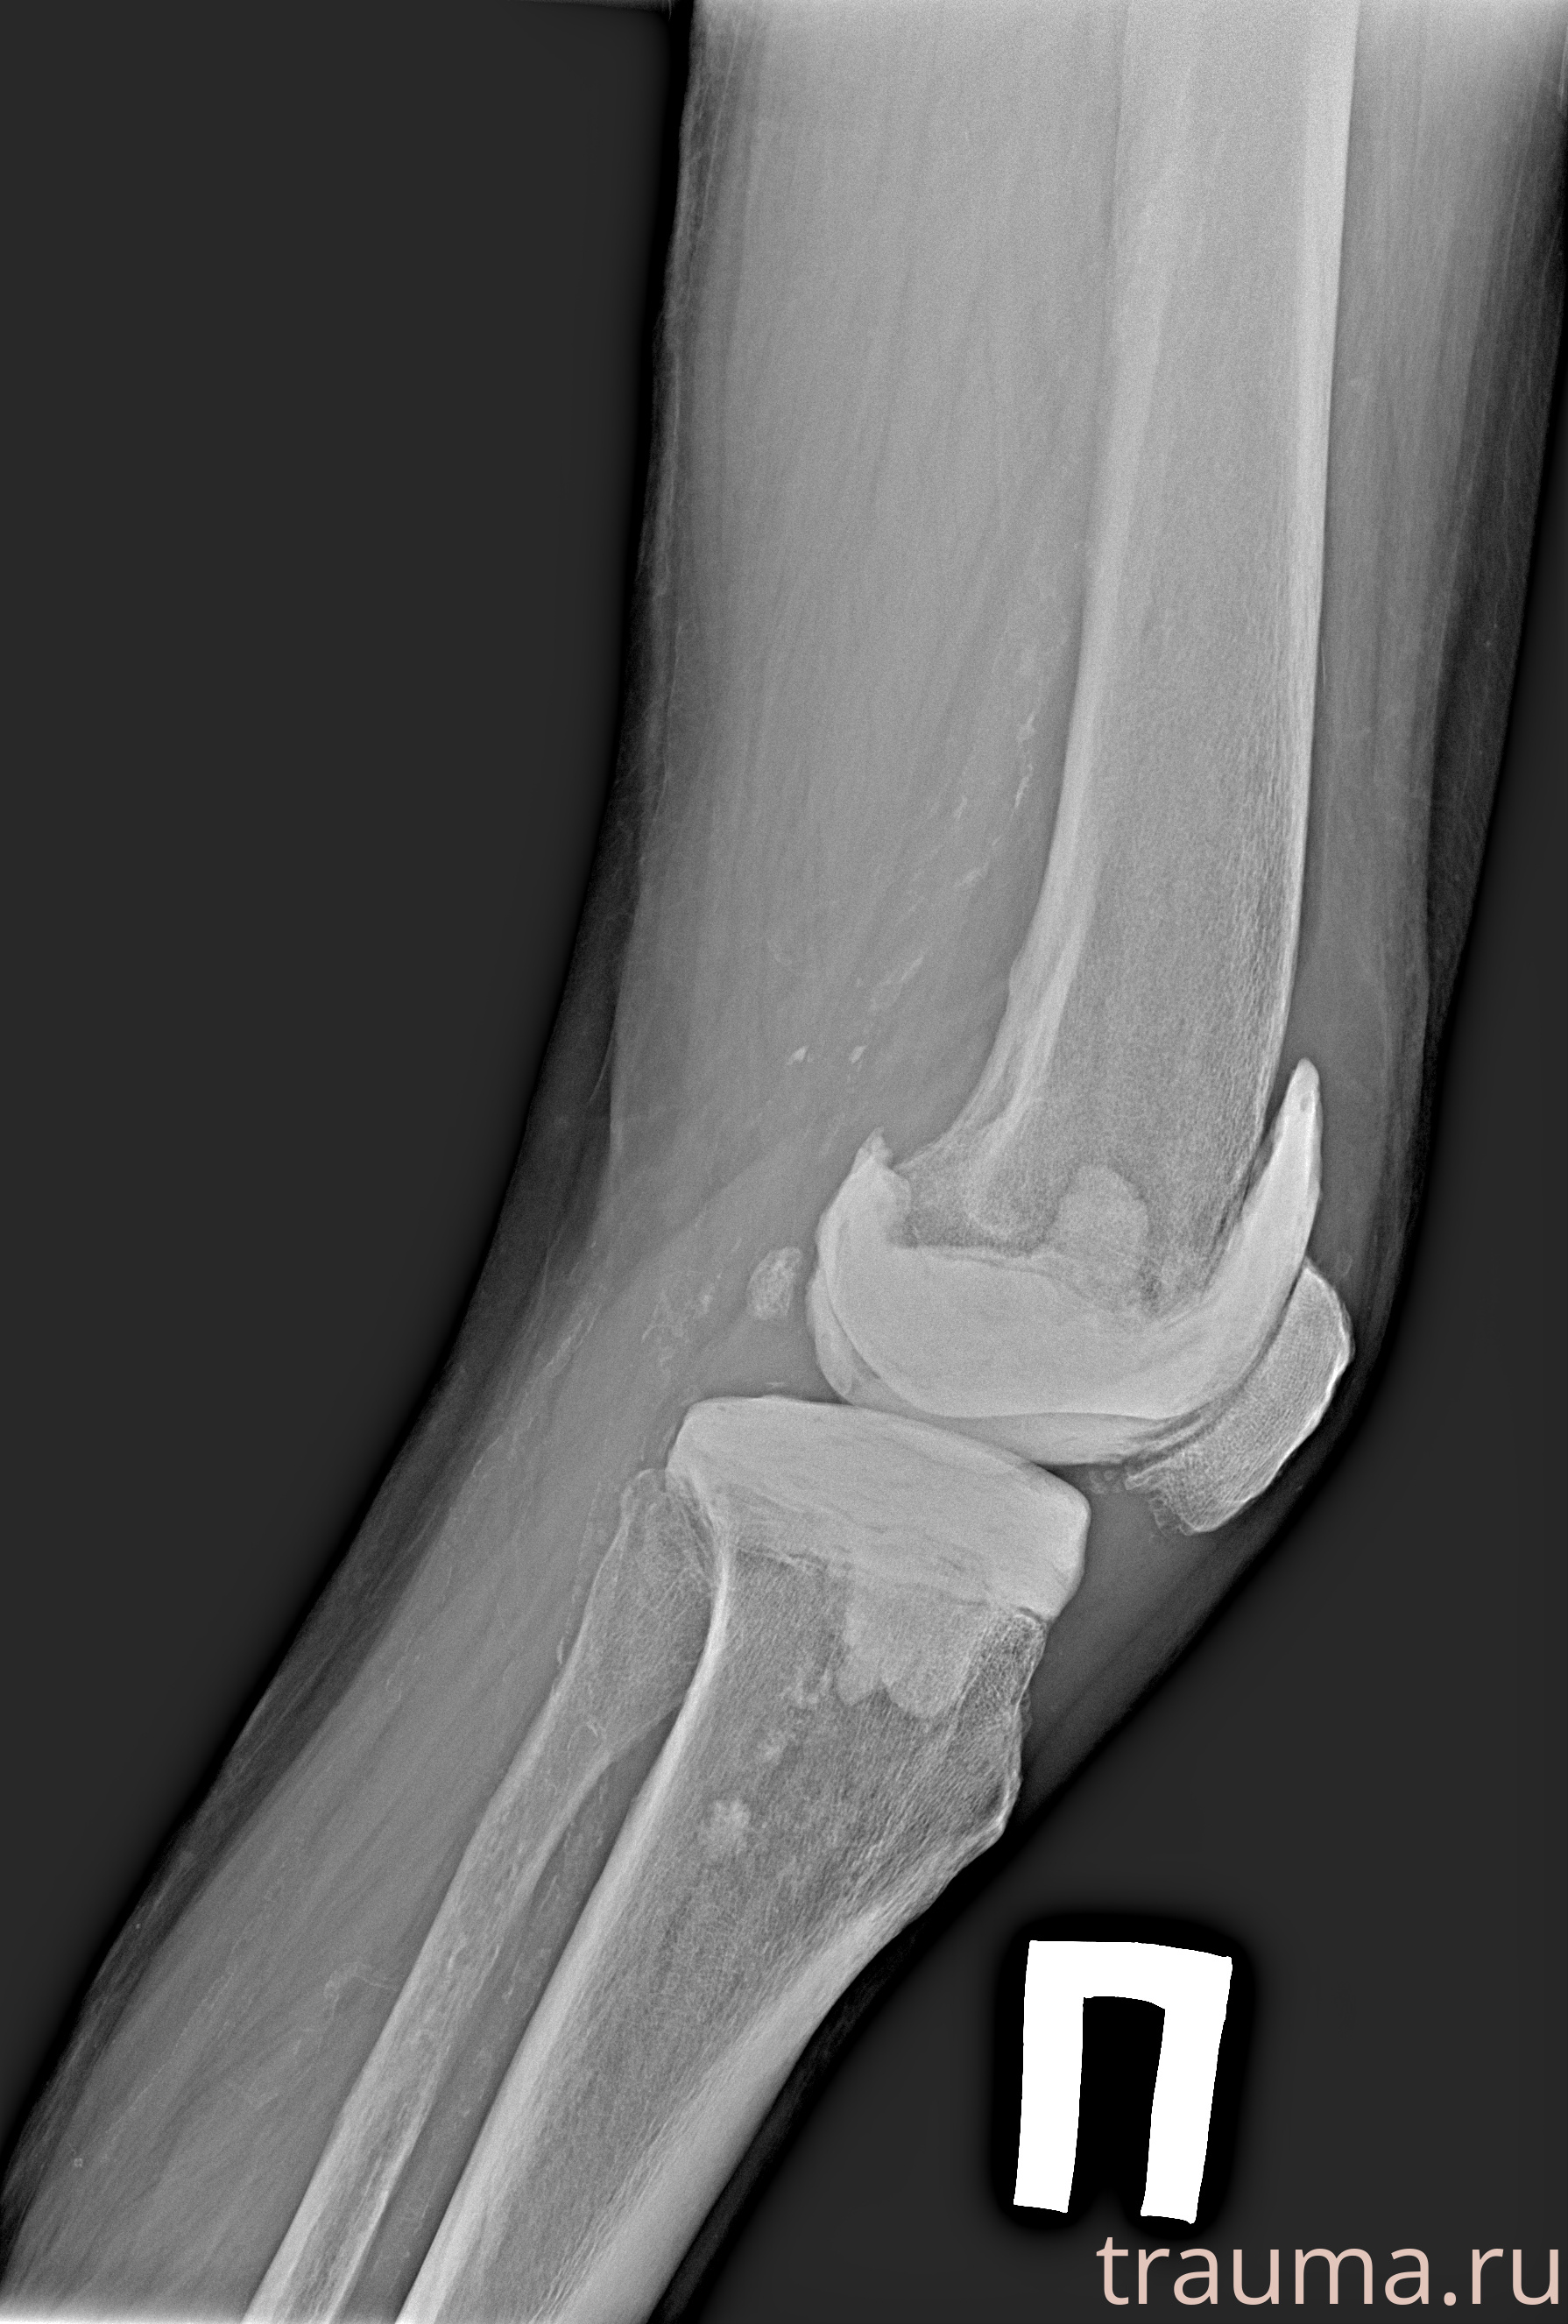

Рентген на дому: по вашему адресу приезжает врач-рентгенолог, травматолог-ортопед с мобильным рентгеновским аппаратом, проводит диагностику травмы или заболевания, делает необходимые рентгенограммы, дает рекомендации по дальнейшему лечению. Получить качественные снимки в домашних условиях возможно благодаря уникальной методике, разработанной МосРентген Центром для института  Склифосовского